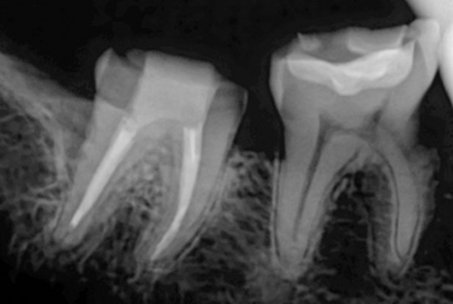

위 사진들은 현직 치과의사들이

저희 웃는얼굴 치과에서 치료 받은 실제 사례들입니다.

비 전문가 눈에는 그냥 흔한 엑스레이 사진일 뿐이겠지만

치과의사들이라면 알아챕니다.

저 치료가 얼마나 난이도 있는 치료였는지,

얼마나 정성이 들어갔는지를 말이지요.

외과적 신경치료라 불리는 치근단 절제술은

재신경치료가 불가능한 경우에 행해지는 전문적인 시술입니다.

잇몸을 열고 염증의 원인이 되는 치아뿌리를 3MM 잘라낸 후

MTA라는 특수충전재료로

뿌리 끝부분을 충전하는 술식입니다.

치근단절제술은 치근단절제술 전용 특수기구와 MTA라는

특수재료를 사용해야만

제대로 된 치료가 이뤄질 수 있습니다.